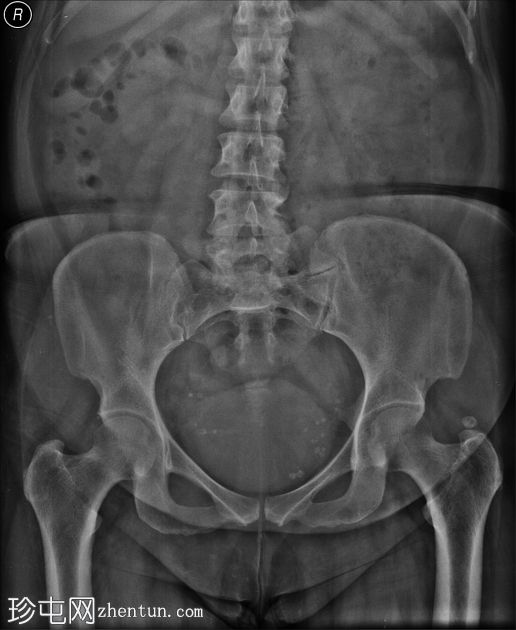

纵切面

5.jpg

经会阴超声显示尿道外口附近尿道内有一强回声灶(9 mm),伴有明显的后方声影。局部血流丰富。未见尿道扩张/尿道周围肿块病变。

由于女性尿道较短,尿道嵌顿结石较为罕见。

该患者因排尿困难就诊,临床怀疑为尿道嵌顿结石,既往有排尿困难病史。患者无腰腹疼痛或血尿病史。经腹部超声检查唯一阳性发现是排尿后尿量明显增多。经会阴超声检查证实了尿道嵌顿结石的临床诊断,随后由外科医生取出结石。